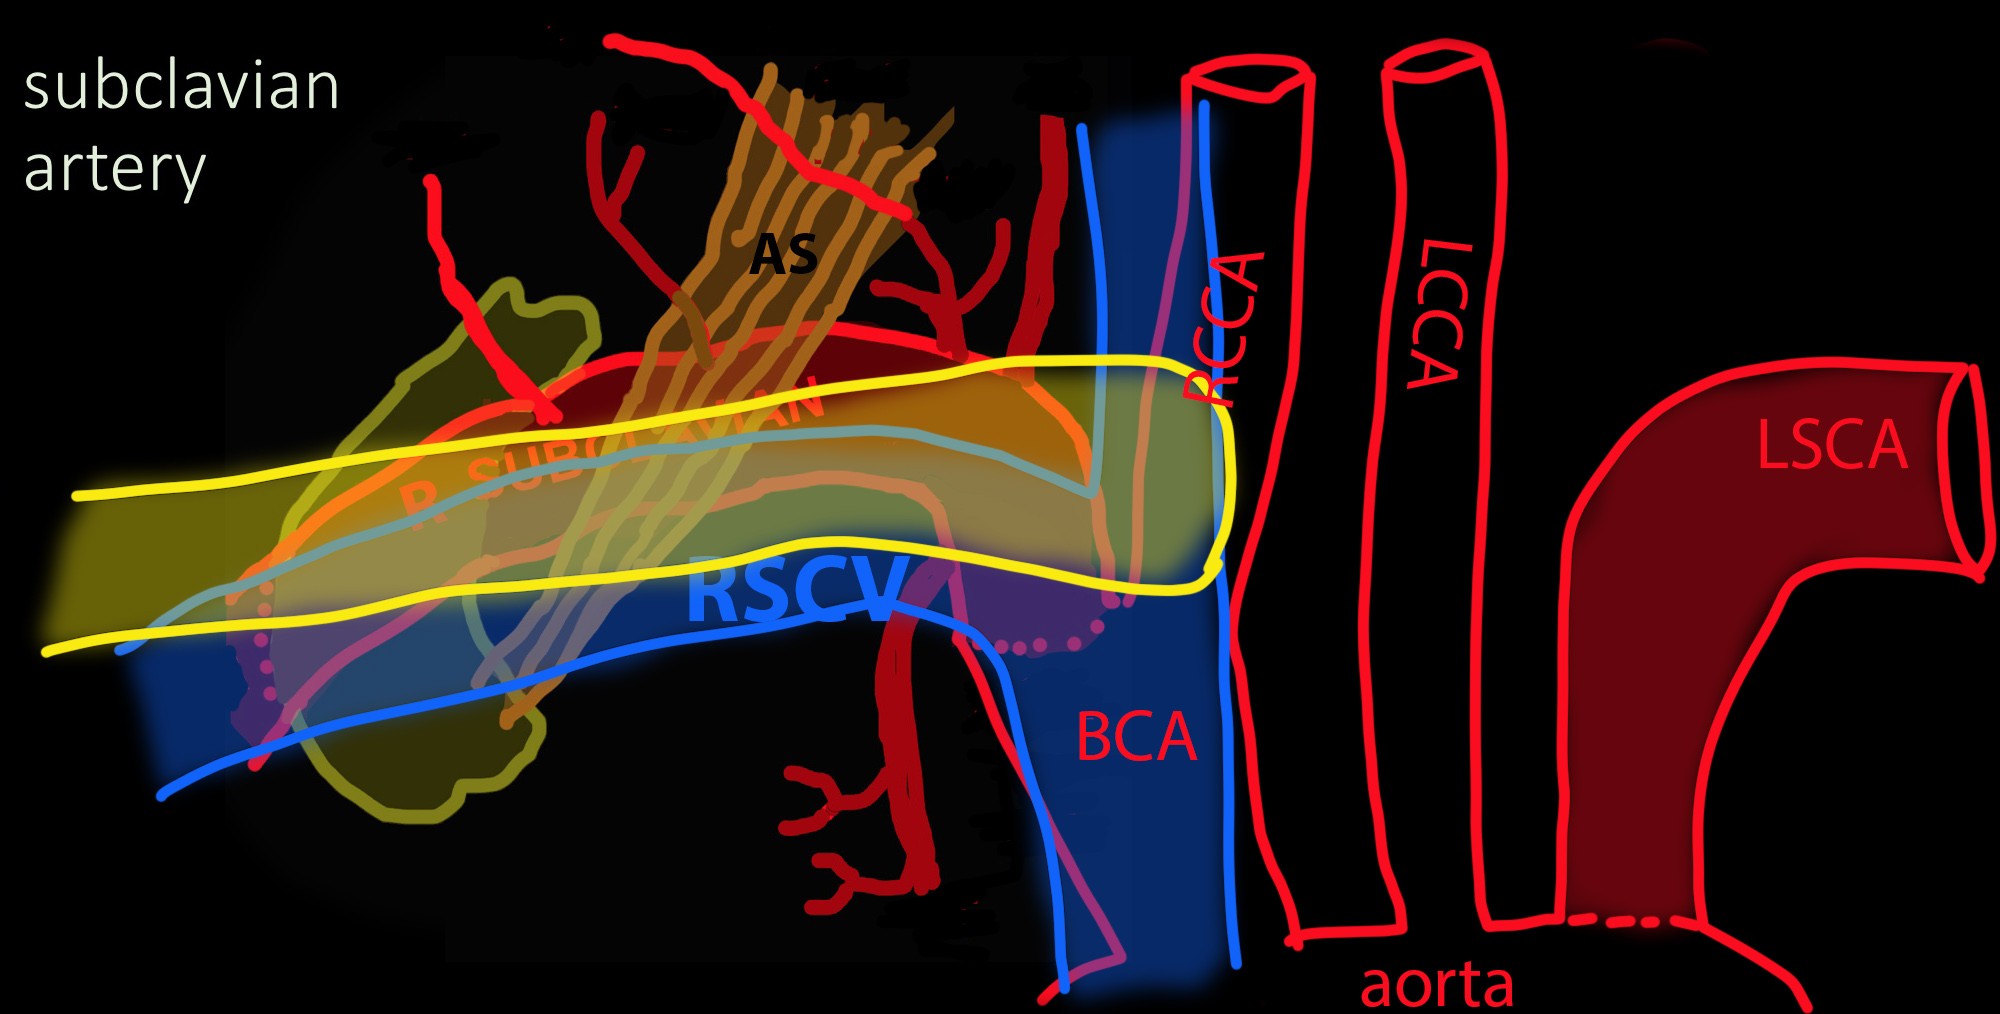

◂Breast Anatomy